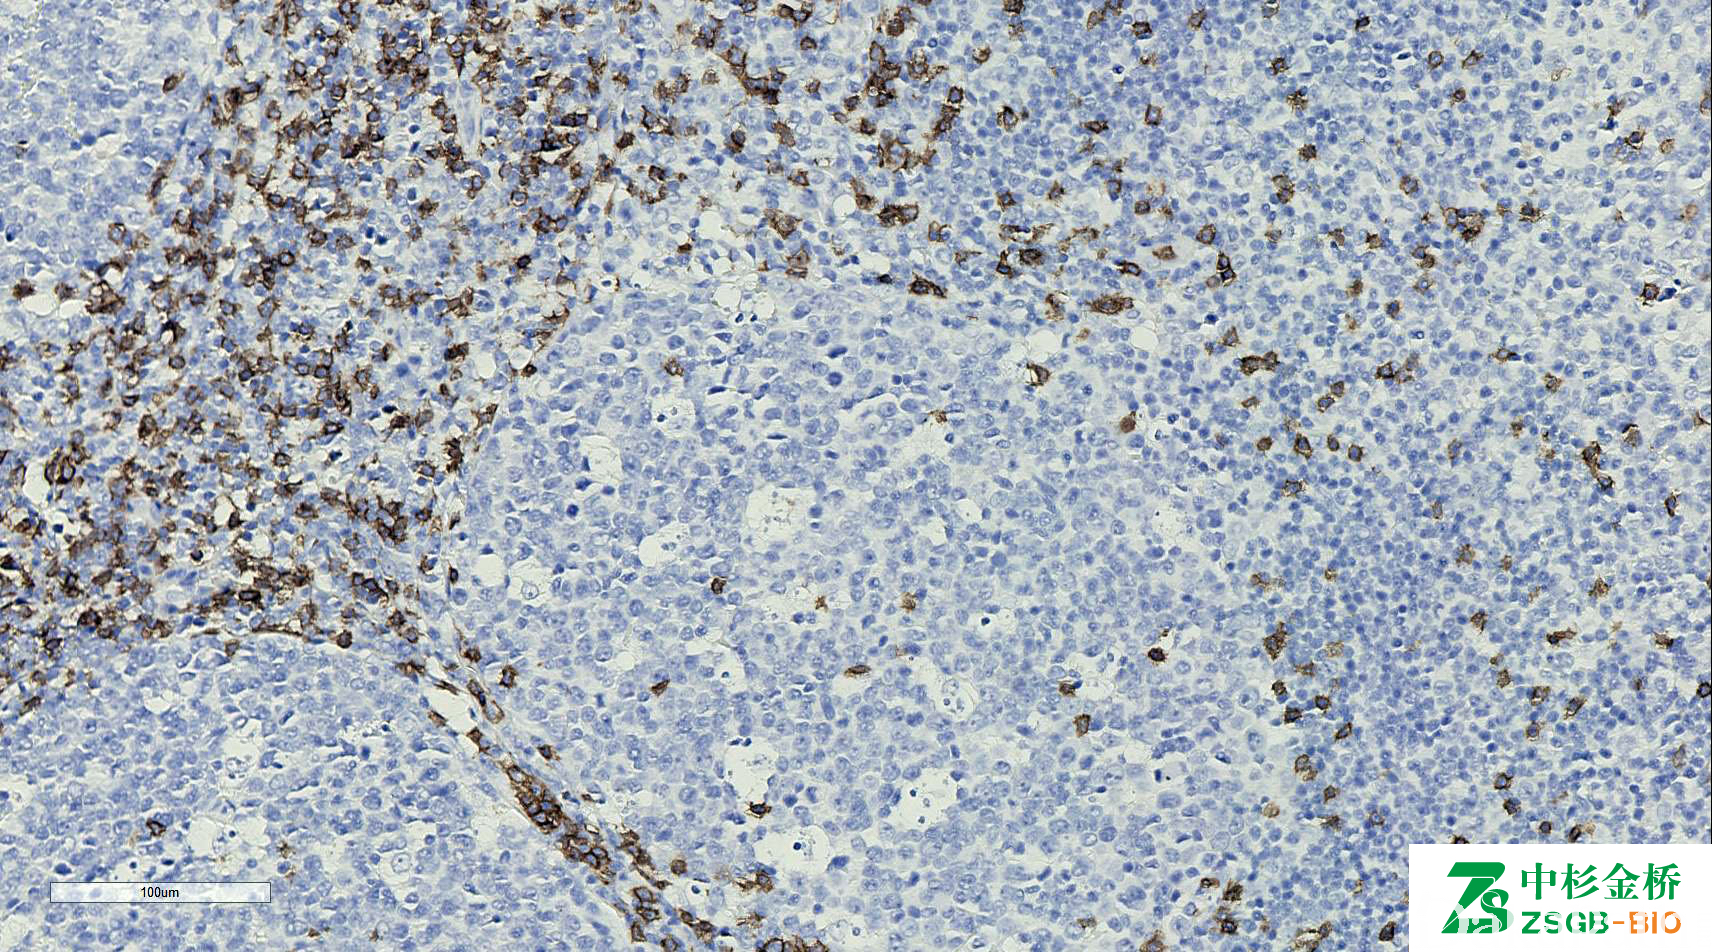

CD8

细胞毒 T 细胞标志物,免疫球蛋白超家族成员,一种细胞表面糖蛋白。

信号定位: 胞膜

T 细胞淋巴瘤的诊断及分型。